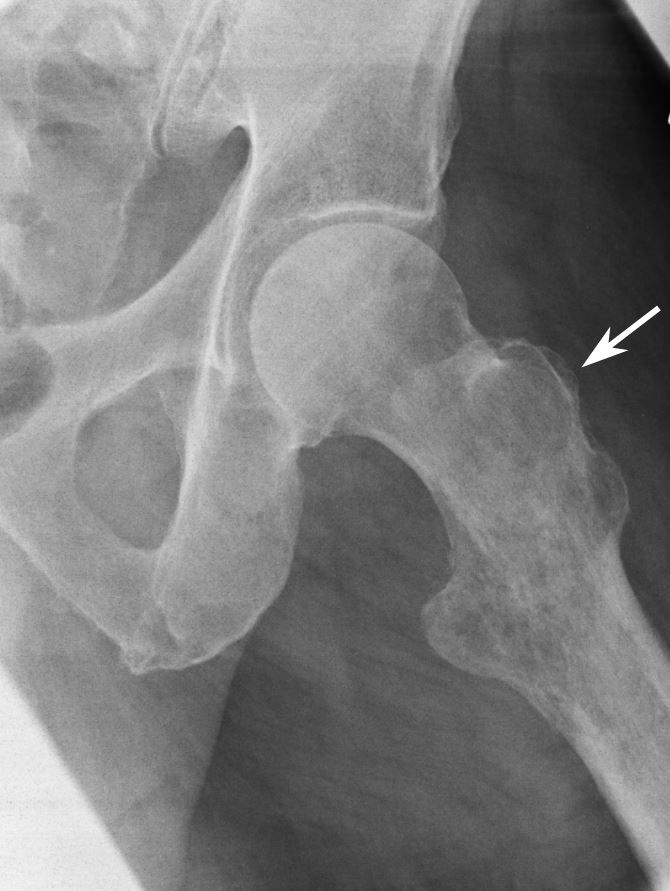

Cureus Clavicular Osteomyelitis Secondary to Candida Parapsilosis

From www.cureus.com

Cureus Clavicular Osteomyelitis Secondary to Candida Parapsilosis Collar Bone Lump Lymphoma A common lymphoma symptom is lumps. Usually, these lumps are benign (non. These are swollen lymph nodes (glands). Possible causes of a lump on the collarbone include a collarbone fracture, infection of the bone (osteomyelitis), enlarged lymph nodes, and a cyst. The most common symptom of hodgkin lymphoma is one or more swellings or lumps in the neck or above. Collar Bone Lump Lymphoma.